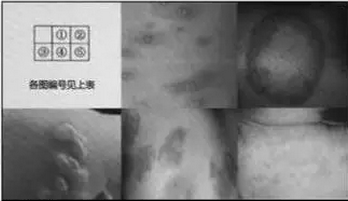

如图所示,属于风湿热特殊皮肤表现的是( )。

A.图4

B.图1

C.图3

D.图5

E.图2

正确答案是E